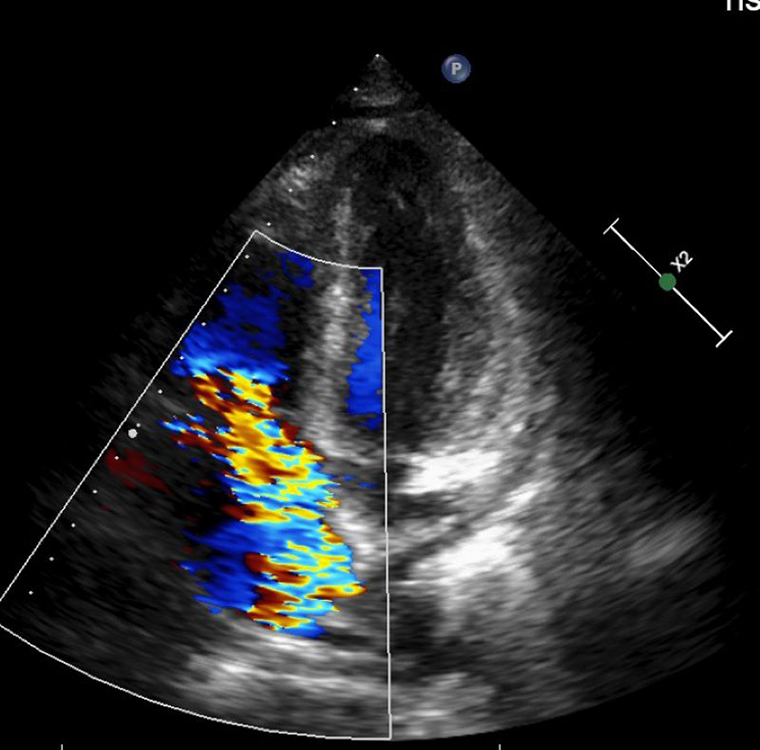

▲影像檢查發現三尖瓣逆流。(圖/台北慈濟醫院提供)

楊凱文醫師表示:「三尖瓣逆流大多可以用藥物控制,若是進展為重度逆流且藥物治療效果不彰,同時合併右心室功能異常,就會需要手術,但臨床案例不多。」診斷上,會以超音波檢查為主,手術則會視病人狀況選擇開胸或微創手術。以林先生為例,考量病人血球數值極低、免疫力差,擔心術中出血,醫療團隊以開胸手術替其更換人工瓣膜,並同步清除感染的贅生物。